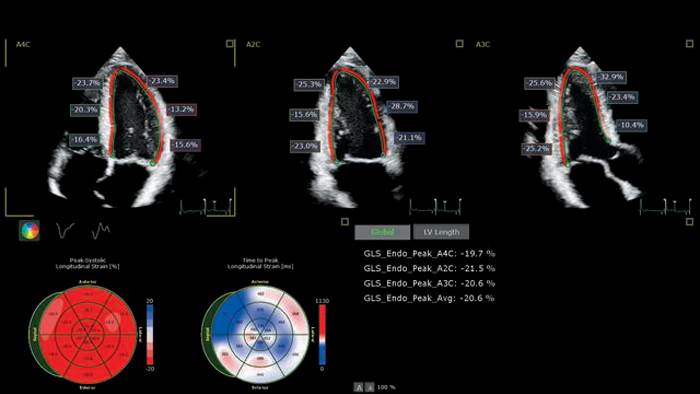

AutoSTRAIN

TOMTEC AutoSTRAIN bietet eine einfache Lösung zur Strain-Messung mit einem einzigen Knopfdruck und mittels Auto View Recognition und Auto Contour Placement mit einer Lernkurve von mehr als 6000 Bildern, um die Zuverlässigkeit zu stützen. AutoSTRAIN ermöglicht schnelle und reproduzierbare Messungen des linksventrikulären, globalen longitudinalen Strains (GLS) für die tägliche klinische Anwendung.